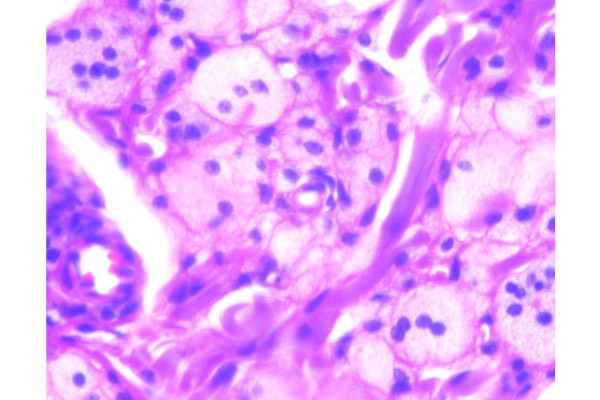

Los macrófagos se transforman en células gigantes, cuyo citoplasma está lleno de vacuolas microscópicas.

Las células espumosas muestran límites celulares evidentes y el citoplasma microvacuolado.